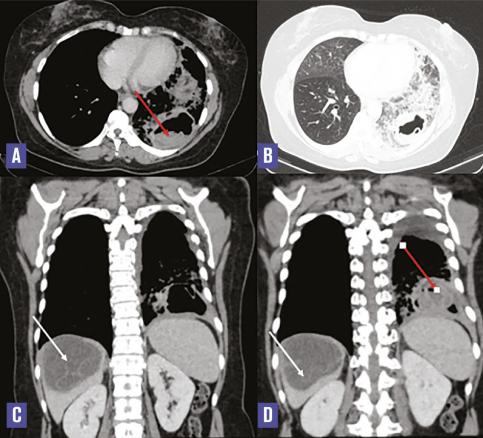

Cette femme de 40 ans consultait aux urgences pour des douleurs basi-thoraciques associées à une pesanteur de l’hypochondre droit. À l’examen clinique, elle était fébrile (38,5 °C) et polypnéique. Le bilan biologique montrait un syndrome inflammatoire. Sur la tomodensitométrie thoraco-abdominale (v. figure ) on notait deux masses pulmonaires du lobe inférieur gauche dont une était excavée, à paroi épaisse irrégulière et renfermant une membrane décollée et flottante (flèche rouge). Au niveau hépatique, il y avait une masse kystique à paroi fine du dôme, renfermant de multiples cloisons (flèche blanche). Après une chimiothérapie par albendazole, une résection chirurgicale des trois kystes était réalisée, l’étude histologique confirmant le diagnostic d’hydatidose.

La maladie hydatique est une infection parasitaire endémique due au développement chez l’homme de la forme larvaire d’Echinococcus granulosus.1 L’hydatidose multiviscérale, définie par la localisation simultanée de kystes hydatiques dans plus d’un organe, est peu fréquente. Elle pose des difficultés diagnostiques étant donné son polymorphisme d’où l’intérêt de réunir un faisceau d’arguments cliniques, sérologiques et radiologiques pour retenir le diagnostic. L’imagerie joue un rôle important dans le diagnostic positif, la recherche de complication et dans le bilan de surveillance. Le traitement est fondé essentiellement sur la chirurgie.2